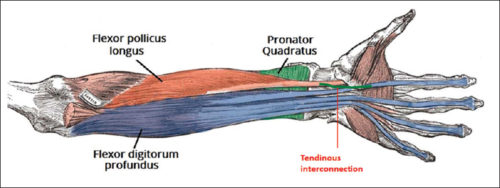

神经肌肉电刺激治疗上肢瘫痪

使用神经肌肉电刺激治疗上肢瘫痪作者:Mikayla Murphy Martin, R.、Johnston, K. 和 Sadowsky, C. (2012)。神经肌肉电刺激辅助抓握...